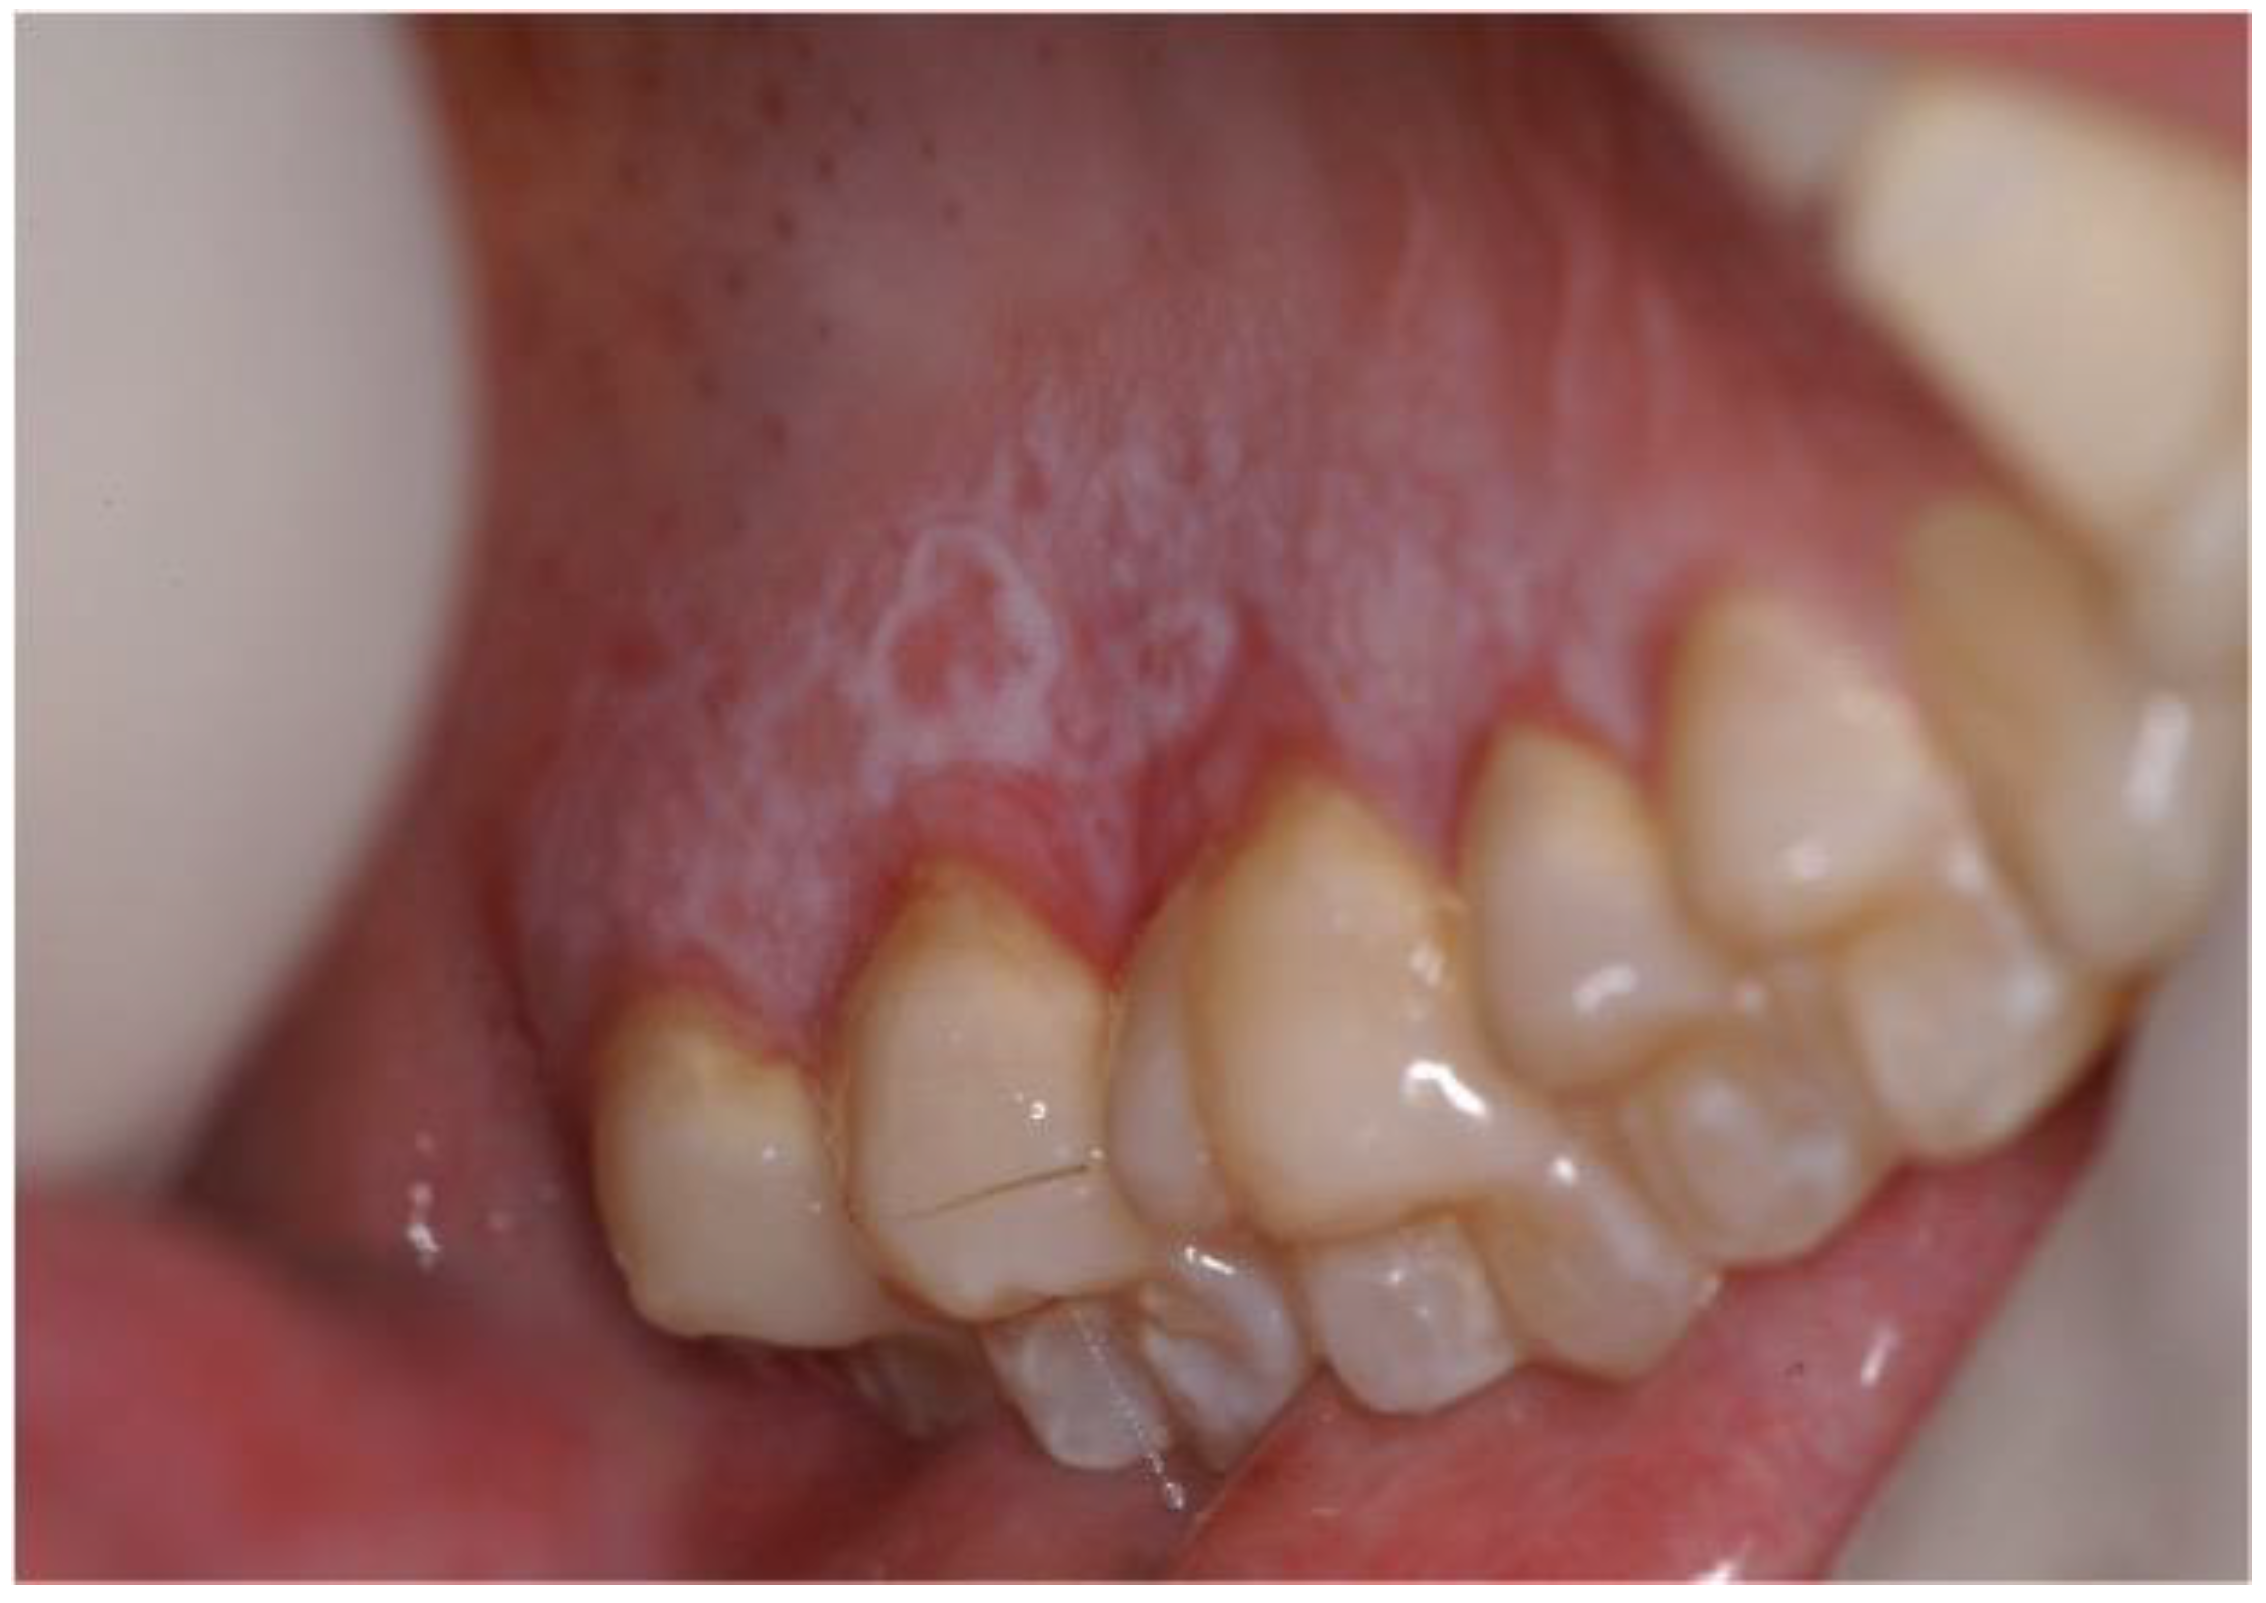

- Elad, S.; Aljitawi, O.; Zadik, Y. Oral Graft-Versus-Host Disease: A Pictorial Review and a Guide for Dental Practitioners. Int. Dent. J. 2021, 71, 9–20. [Google Scholar] [CrossRef] [PubMed]

- Gomes, A.O.; Torres, S.R.; Maiolino, A.; Dos Santos, C.W.; Silva Junior, A.; Correa, M.E.; Moreira, M.C.; Gonçalves, L. Early and late oral features of chronic graft-versus-host disease. Rev. Bras. Hematol. Hemoter. 2014, 36, 43–49. [Google Scholar] [CrossRef]